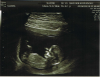

C'était le grand jour !

9 semaines et demi.

Prochain rdv le 26 mars avec un généticien pour echographie et screenings.